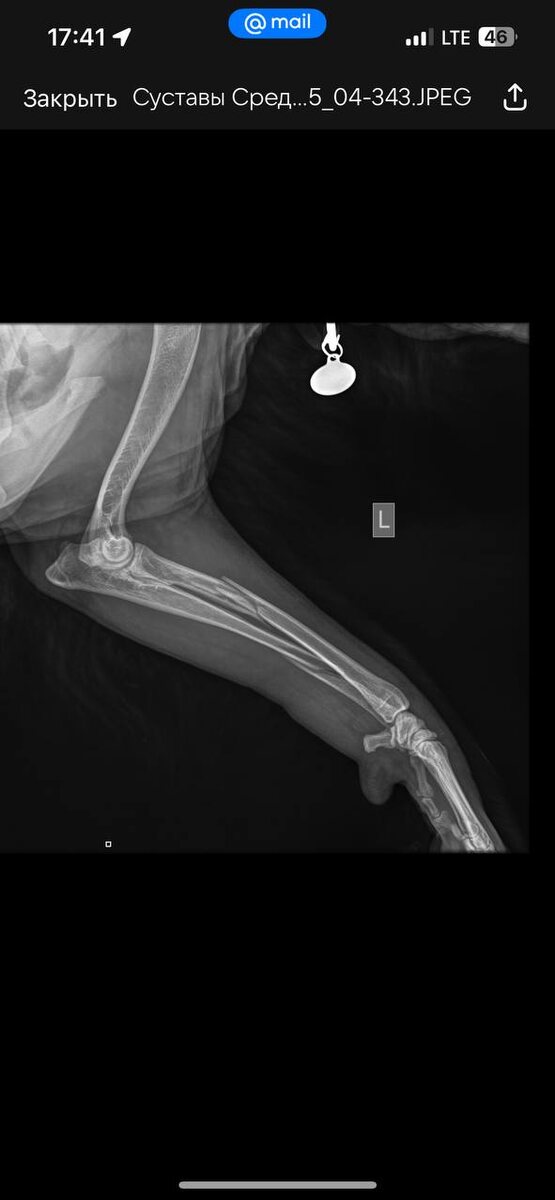

Луна сломала переднюю лапу. Непринужденно, легко, дома 🙈 Перепрыгнув щенячий вольер. Перелом в двух местах, достаточно сложный. Буду делится новостями и полезными советами, сталкиваемся впервые. Едем на консультацию к одному из лучших ортопедов 🫡

Важно: Некоторые трещины в кости (неполные переломы) могут проявляться лишь сильной хромотой, без явной деформации. Поэтому любая внезапная и серьезная хромота после травмы — повод для срочного визита к ветеринару и проведения рентгенографии.